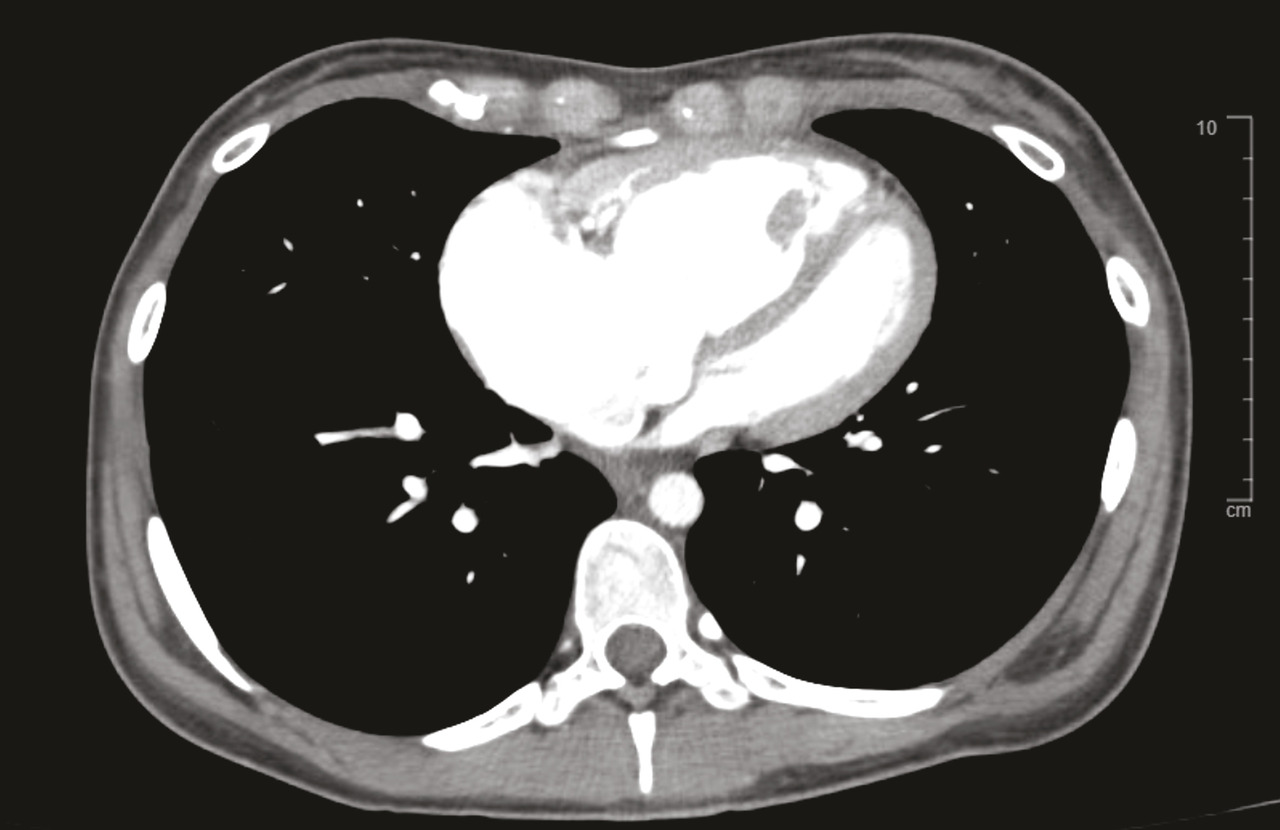

Les marqueurs cardiaques tels que le BNP (Brain natriuretic peptide) et/ou le NT-proBNP (N-terminal pro-brain natriuretic peptide) peuvent être augmentés en cas d’HTP. Ces biomarqueurs sanguins sont également utilisés dans le cadre du suivi des patients atteints d’HTP, une fois le diagnostic confirmé.Radiographie thoracique

La radiographie thoracique montre généralement une dilatation des artères pulmonaires proximales et un élargissement des cavités cardiaques droites (oreillette et ventricule droit) [Épreuves fonctionnelles respiratoires